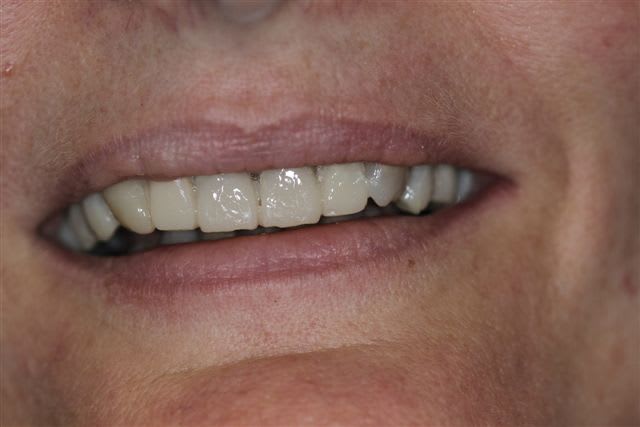

N'hésitiez pas çà me donner votre avis, patiente 47 ans ne supporte plus ses antérieurs, maquillées à la résine il y a quelques années.

Pas de demande concernant l'occlusion, ni les postérieurs, à fait des économies et veux s'offrir "un sourire", sur fond propre budget envisageable au départ 4000€

La suite, les soins ont commencés le 07/08.

Postérieur bas (16/08)et haut (14/09) en place, essayage des Emax avec "cutback".

Pour la teinte la patiente exige B1, sans maquillage, elle n'a pas attendu 47 ans pour que ça ne soit pas Blanc de blanc, alors là dessus j'ai cédé.